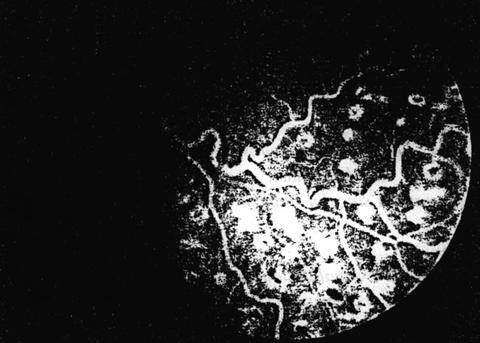

Fig.

2

OVCR - forma ischemica